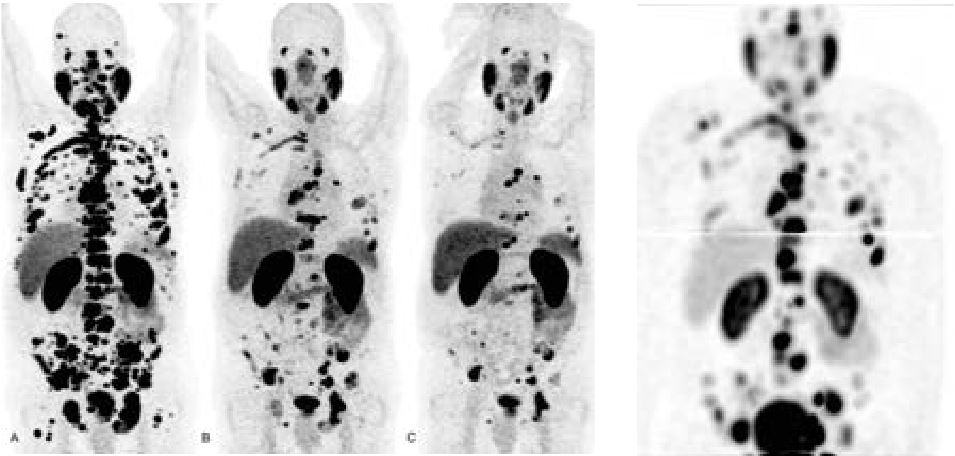

• Oncologie (métastases, tumeurs primitives, réponse au traitement...)

• Par Lutétium 177 dans le cadre du cancer prostatique métastatique

• Par Radium 223, également dans le cancer prostatique métastatique